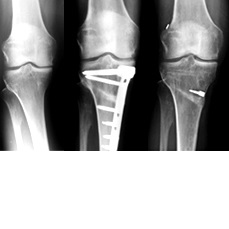

Die Turnweltmeisterschaft im Oktober in Nanning / China sollte jetzt der Höhepunkt werden. Im August dann die Verletzung: eine kombinierte Kapsel-Sehnenverletzung in der Kniekehle nach einer Landung beim Dreifachsalto.

Was tun? Eine Operation oder eine Ruhigstellung hätten die Teilnahme an der WM unmöglich gemacht. Abljasin entschied sich schließlich zu einer konservativen Behandlung in München bei Dr. Kinateder, Kniespezialist im ZFOS, und Cyrus Salehi, Chef–Pysiotherapeut des DTB und Leiter des Consports-Centers. Der Therapie- und Trainingsplan wurde eng abgestimmt mit den Trainern des russischen Turner-Teams. Es war ein guter Plan, wie sich zeigte. Denis Abljasin wurde überraschend Weltmeister am Boden. Mit perfekt gestandenem Dreifachsalto. Zudem wurde er Dritter an den Ringen.